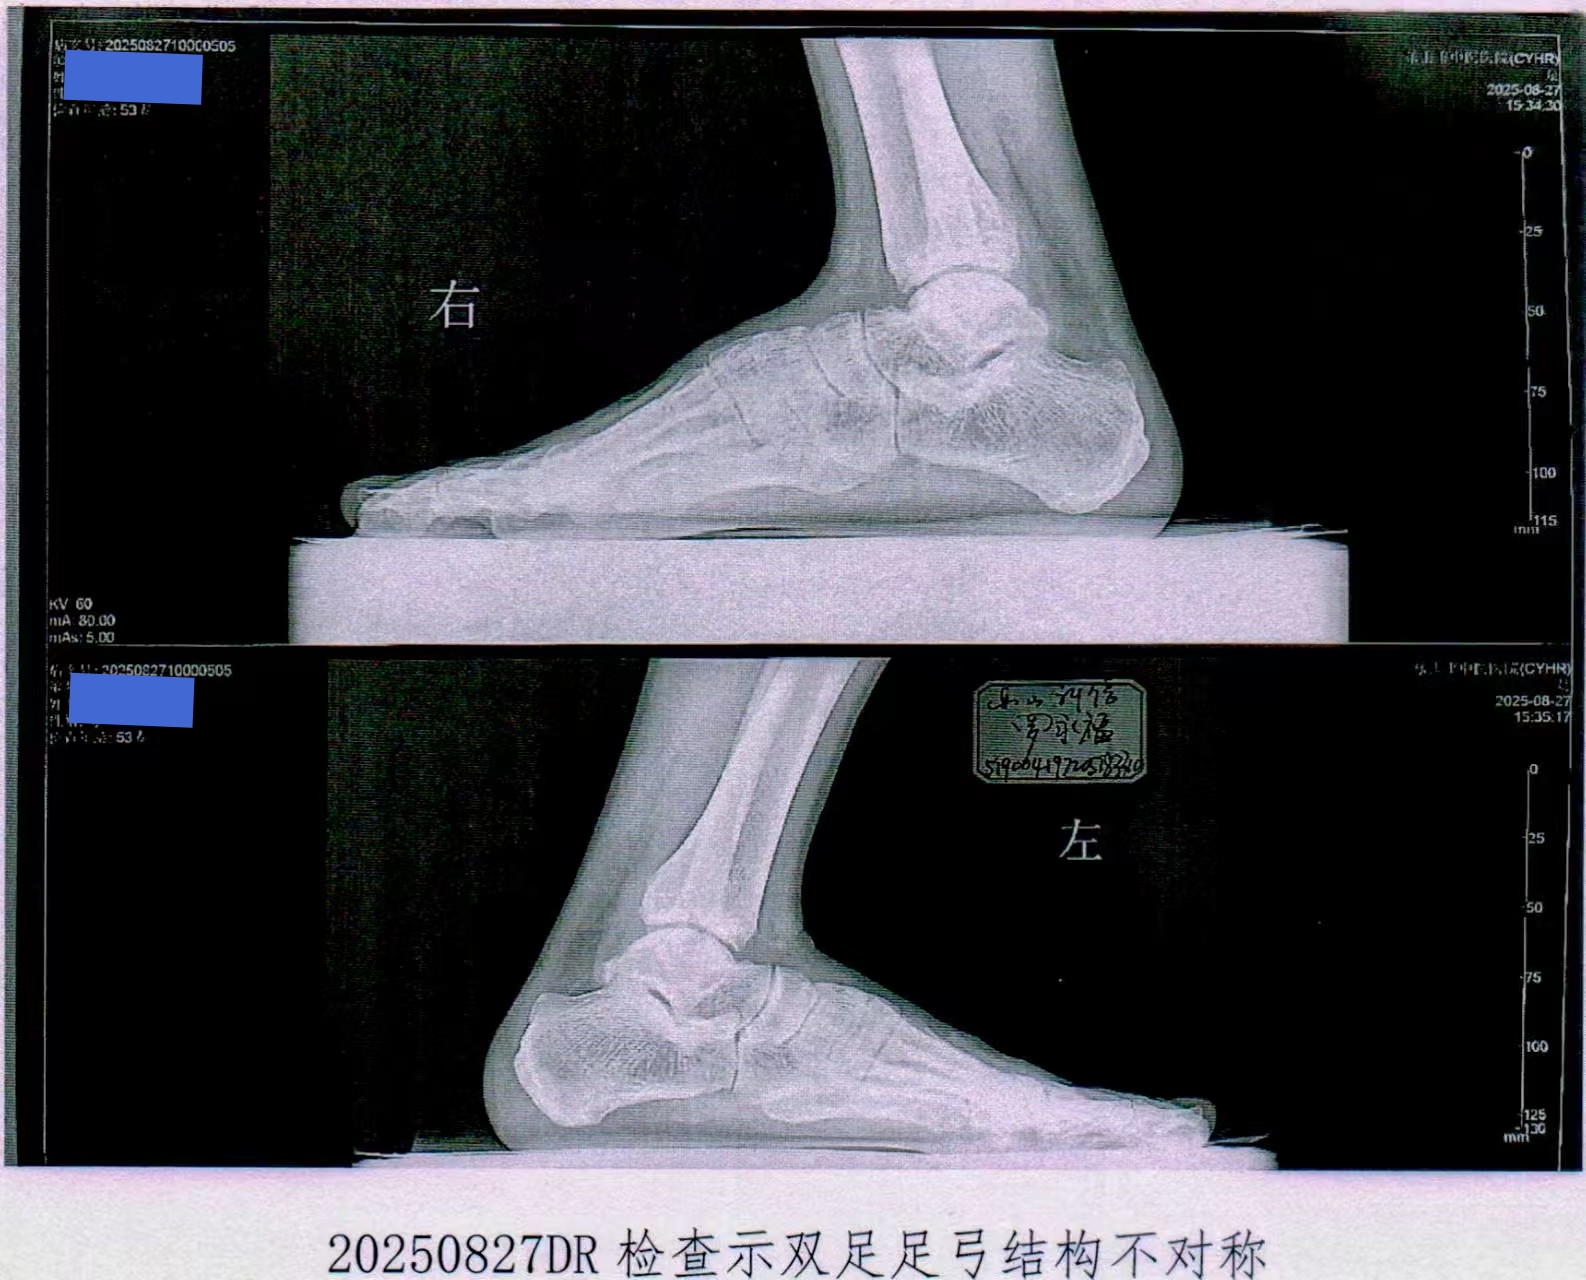

2023年,那曲地区一名建筑工人因意外至脚部受伤至10级伤残,却被保险公司以“非指定机构出具检测报告”为由拒赔。我们协助其整理医疗记录、人身保险伤残证明及专家鉴定,通过3轮协商即成功获赔,全程未进入诉讼程序。